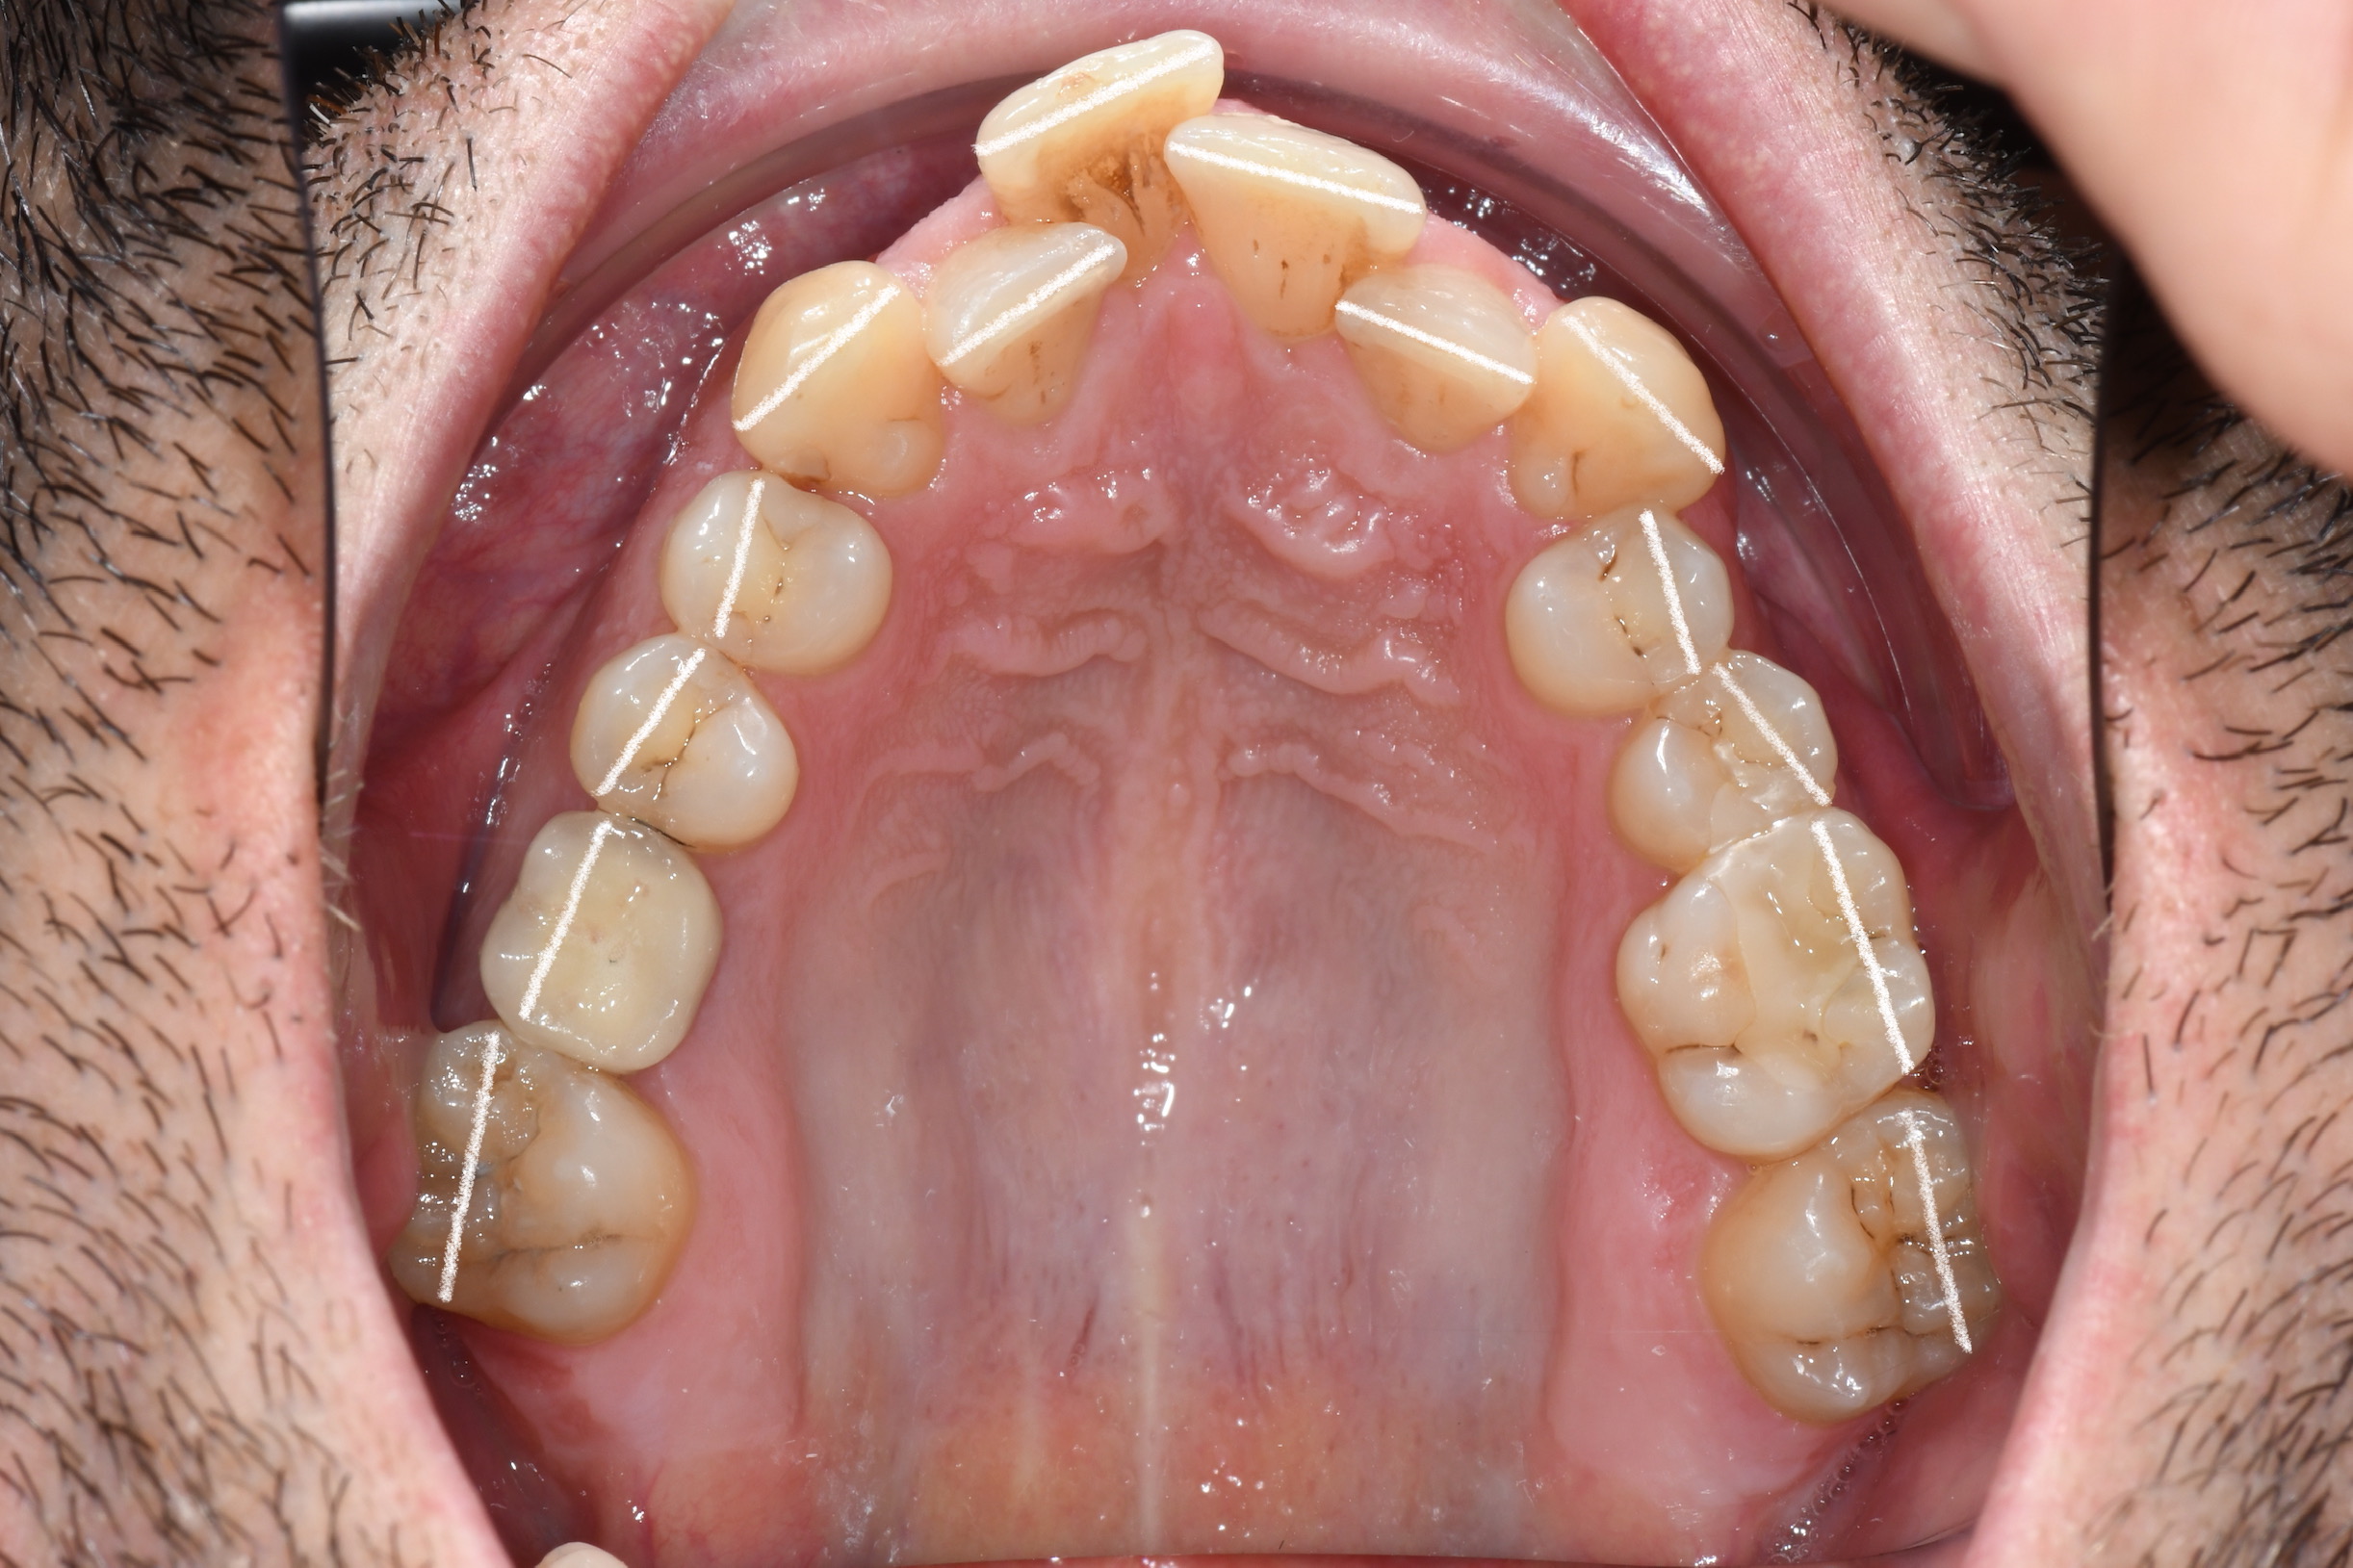

Az elmúlt évekből rengeteg szakmai referenciát tudnánk bemutatni, amelyek különböző fogszabályozási problémákat oldottak meg. Válogatva a több száz esetből, ezen az oldalon olyan képeket, információkat igyekeztünk bemutatni, amelyeknek a segítségével a jövőbeni pácienseinknek azt tudjuk üzenni: A Te fogsorod is lehet gyönyörű!

(Képeket a Pácienseink külön írásos beleegyezésével mutatjuk be!)